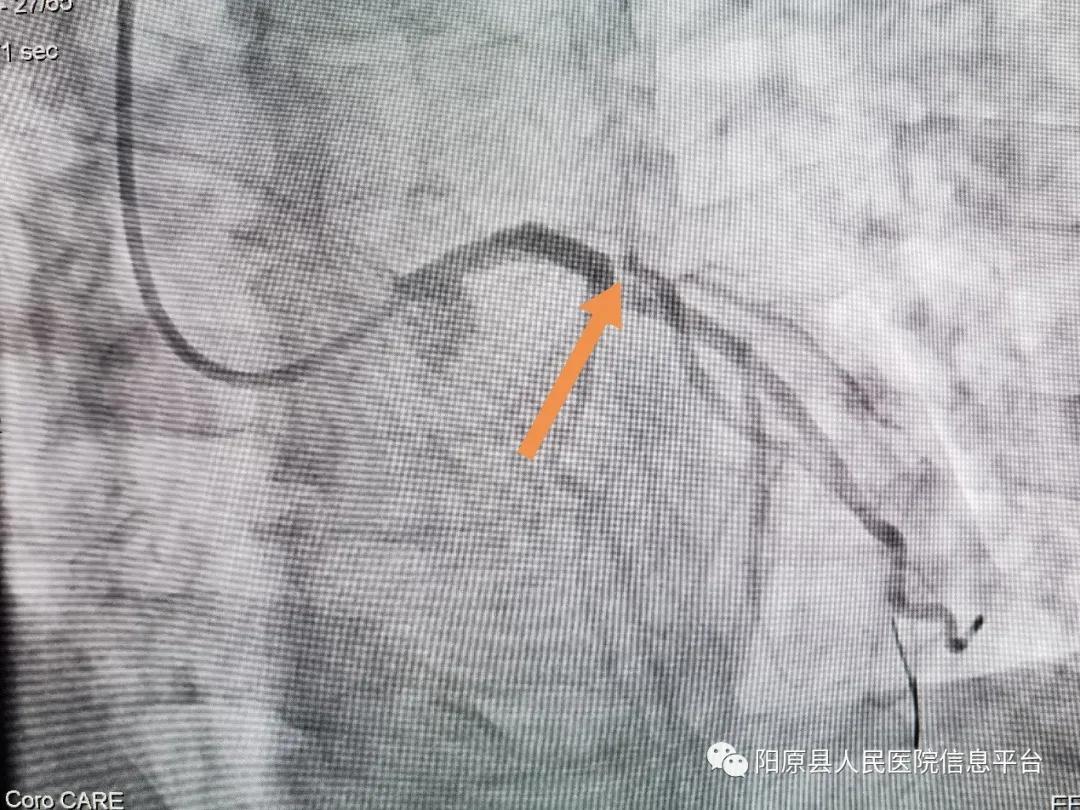

行冠脉造影示: